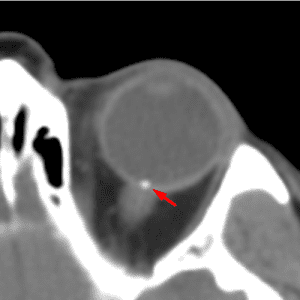

Optic Disc Drusen

Mimicking a foreign body or mass